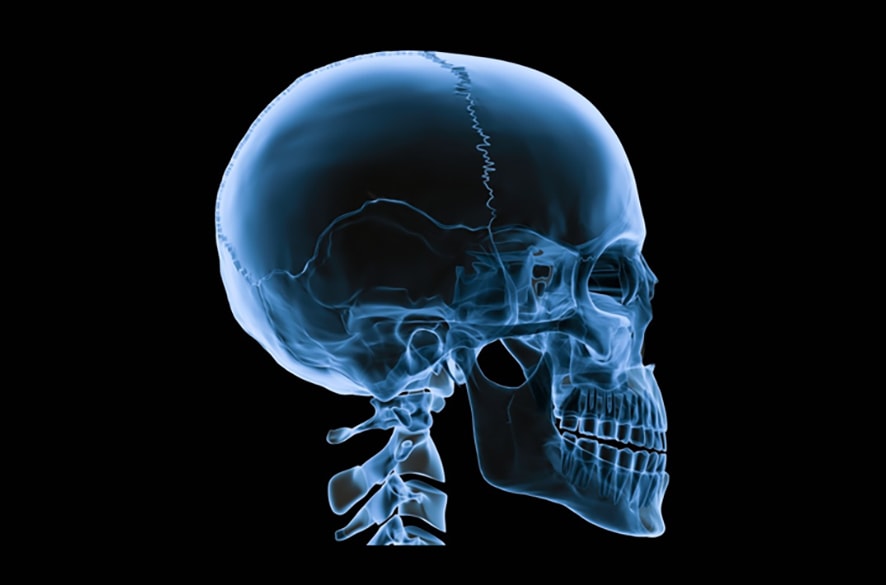

Oral maxillofacial surgeons are specialized professionals who handle complex dental and facial issues. They perform various dental surgeries, including wisdom tooth extraction and other surgical procedures, often under sedation to ensure a smooth recovery process. Their expertise in these dental surgeries makes them the go-to professionals for such intricate procedures.

Complex conditions like impacted wisdom teeth, jaw misalignments, and facial trauma require the expertise of a specialized surgeon.

Facial trauma, whether from an accident or injury, requires the delicate touch of an oral maxillofacial surgeon to restore both function and aesthetics.

These surgeons are equipped to handle everything from minor fractures to major reconstructive surgery.

Their training includes years of surgical residency, focusing on the complexities of facial anatomy and surgical techniques.